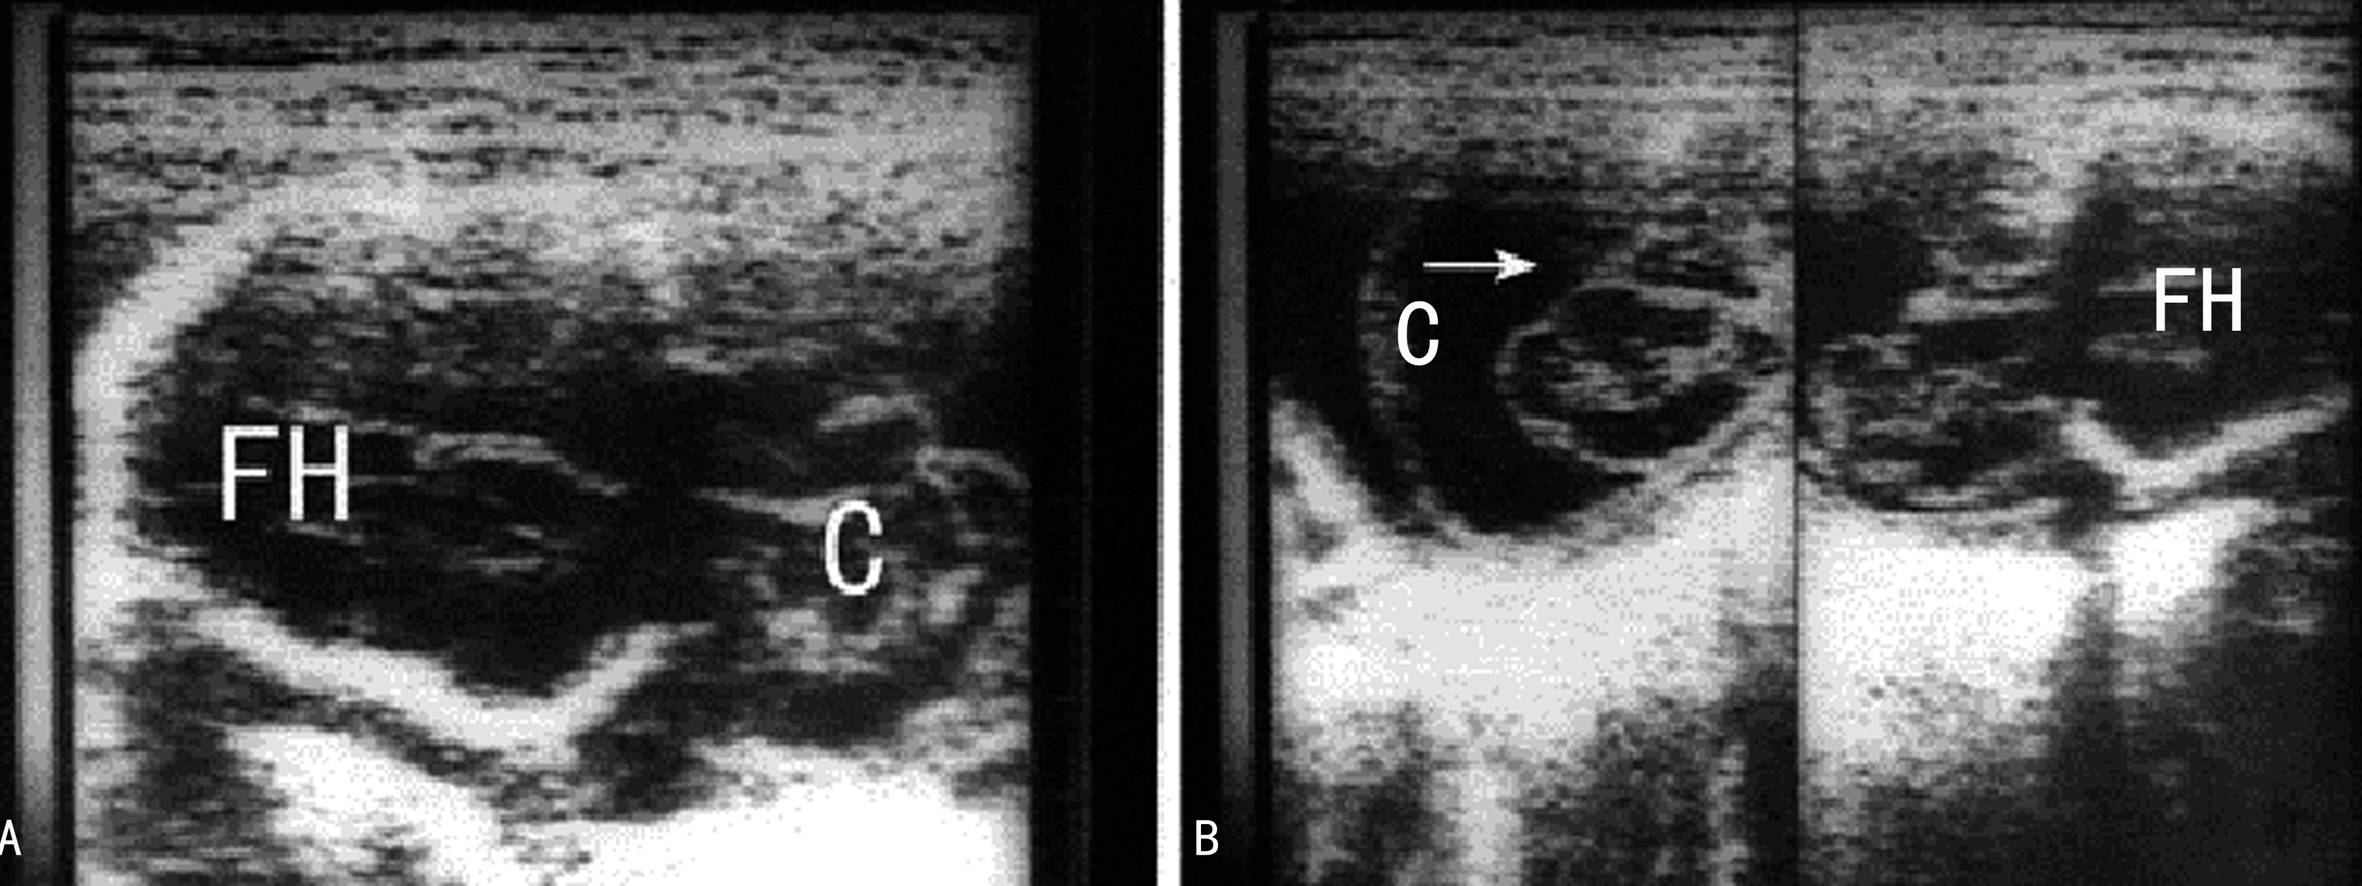

图3 AB示胎儿巨大脑膜脑膨出(C)